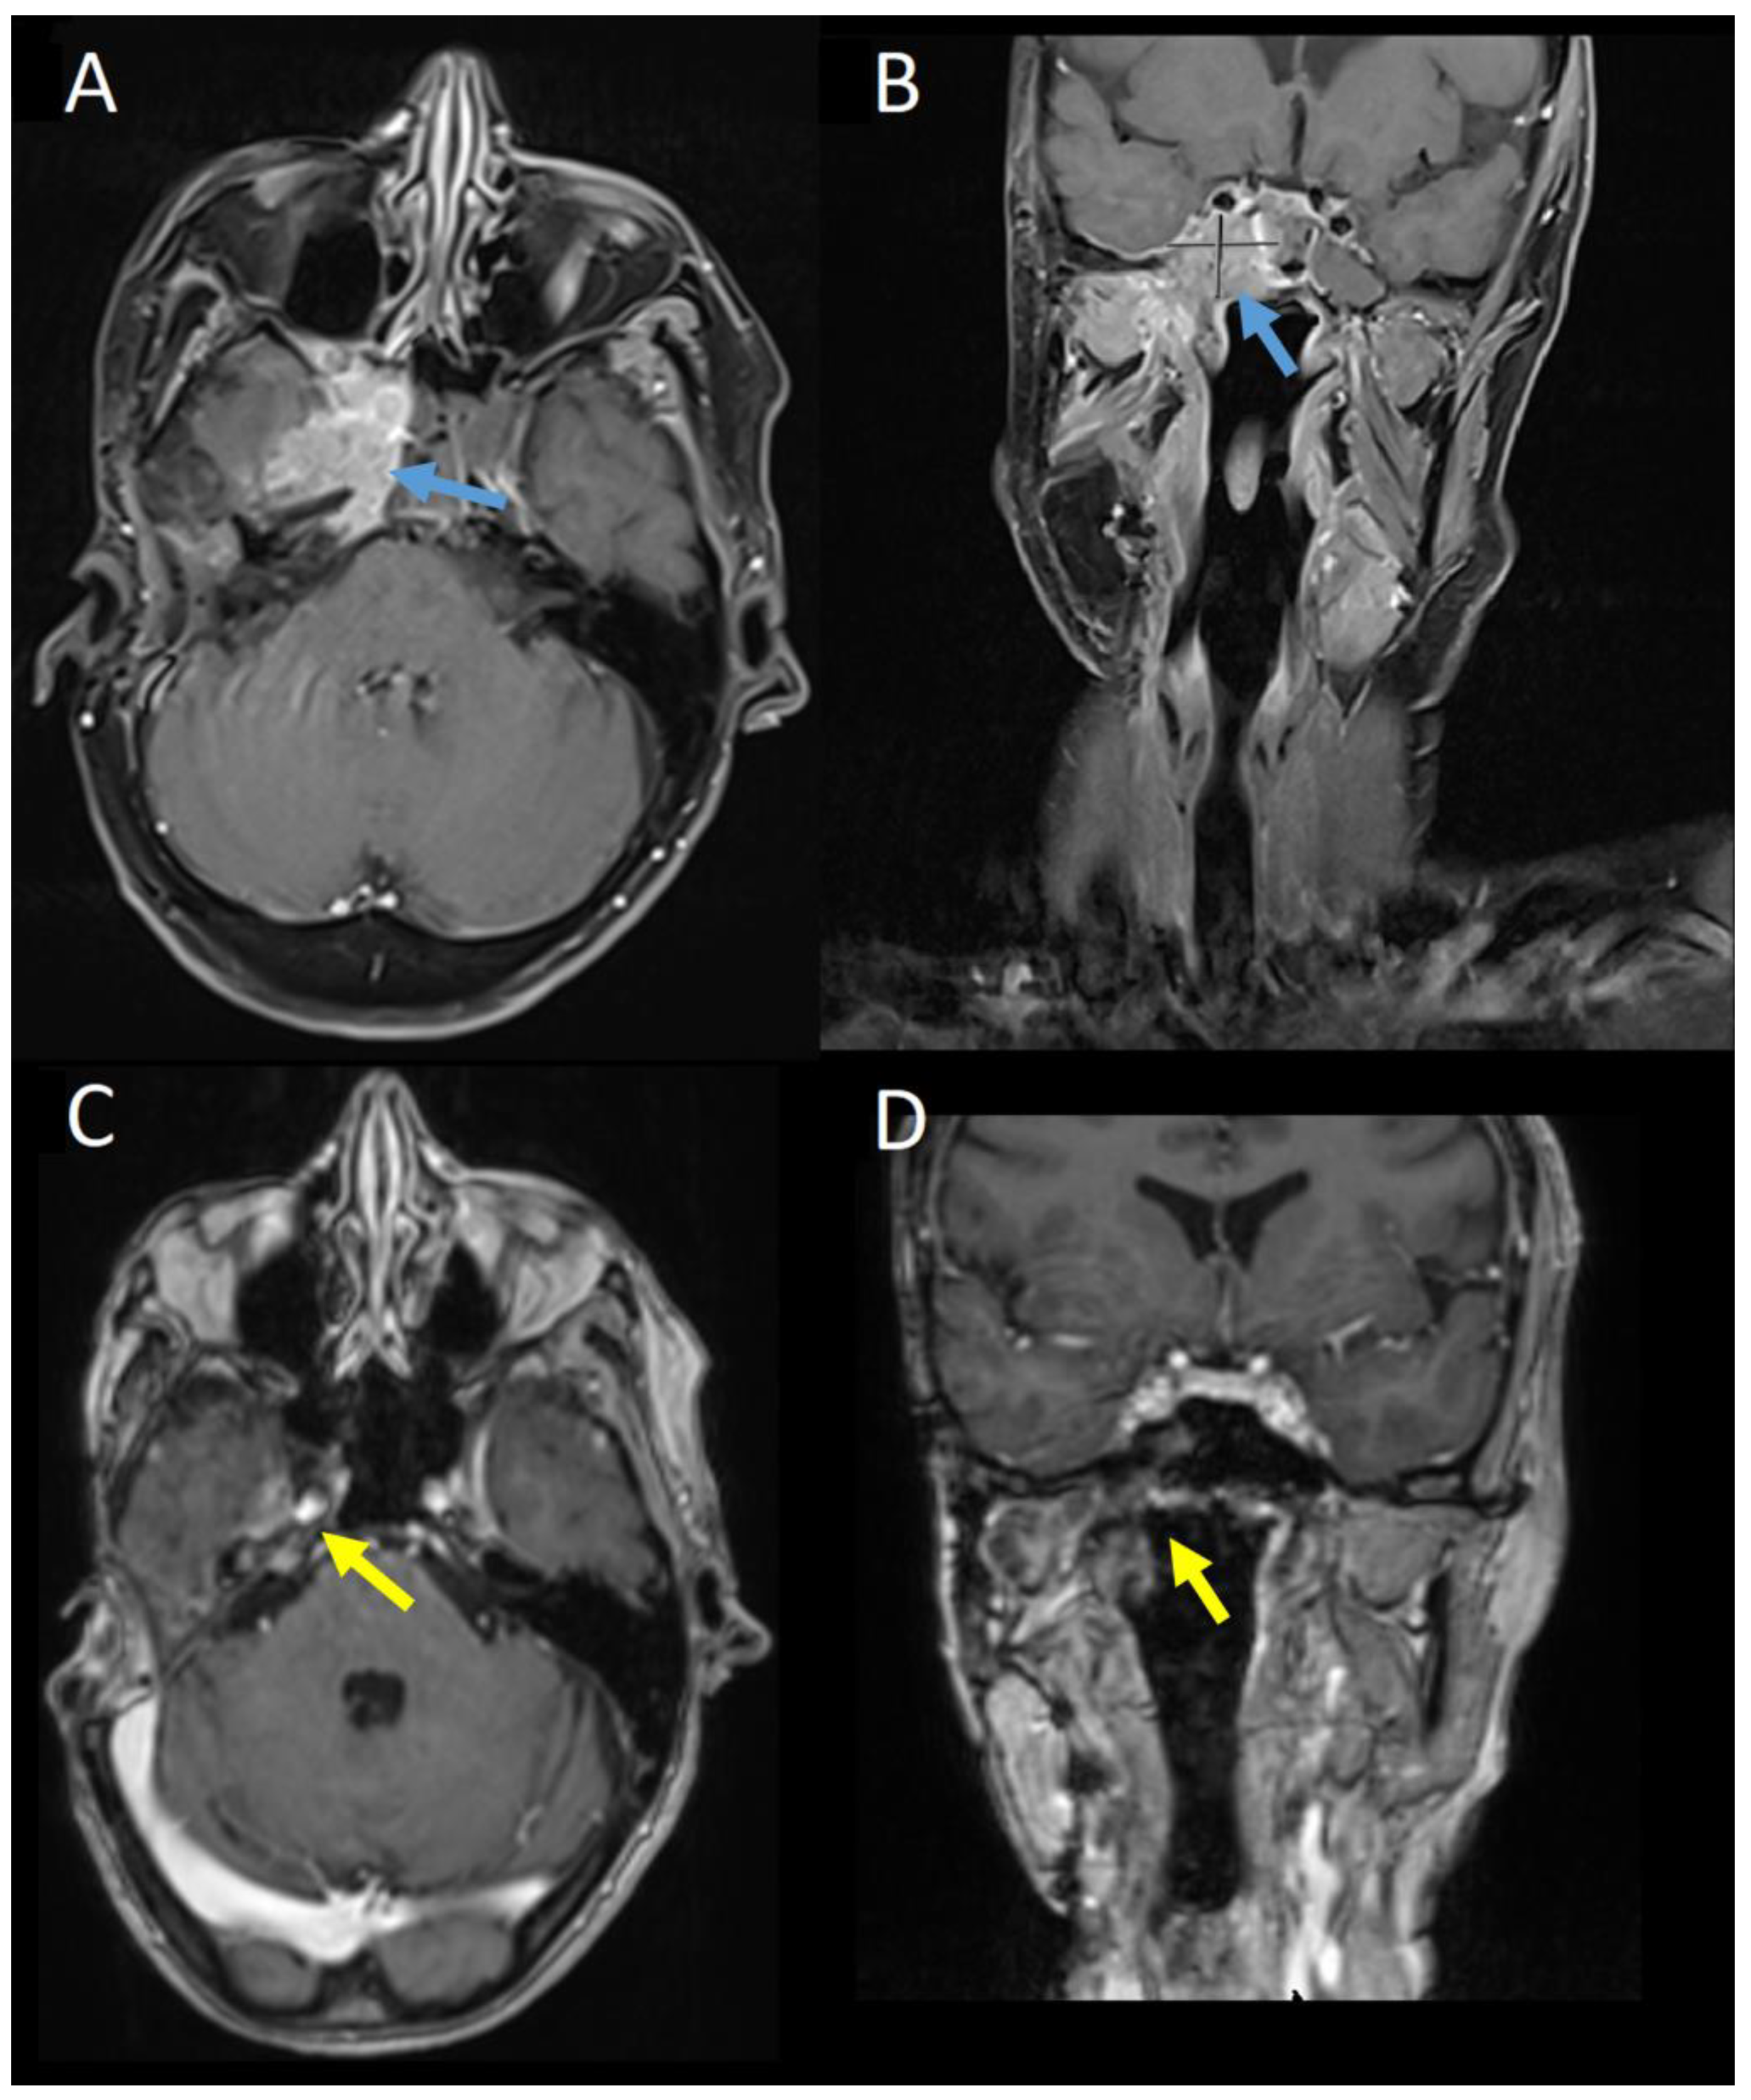

Baseline gadolinium-enhanced MRI head prior to commencing TDM1 showed an unresectable tumour at the right cavernous sinus with involvement of the meninges, clivus, and petrous bone as well as the sphenoid sinus and masticator space (Figure 3A,B). CT with contrast did not demonstrate any distant metastases. Nuclear medicine cardiac ventriculography showed a left ventricular ejection fraction of 70%. Baseline symptoms were facial pain, paraesthesia of the right mandible, and unsteadiness. At this point, further surgery was not possible, and three-weekly TDM1, 3.6 mg/kg, was commenced.

At three months, there was evidence of clinical and radiological response. Gadolinium-enhanced MRI showed the mass centred on the cavernous sinus had reduced from 3.5 × 2.5 cm to 1.9 × 0.7 cm. The patient reported improvement in mobility and resolution of the facial pain. Serial imaging then showed further reduction in disease through to 15 months, from which no measurable disease was visible on MRI imaging. This remained the case on MRI imaging at 38 months post-treatment (Figure 3C,D). Six-monthly nuclear medicine cardiac ventriculography has shown a stable ejection fraction throughout treatment. Nine months after commencing treatment, the patient developed a stable, grade 1 increase in aspartate aminotransferase with no concurrent increase in bilirubin, which continues to be monitored and is considered to be drug-related.

Figure 3. Gadolinium-enhanced MRI scan at baseline in (A) axial and (B) coronal planes and 38 months post-treatment in (C) axial and (D) coronal planes. The enhancing mass centred on the right cavernous sinus in (A,B) (blue arrows) is no longer apparent in (C,D) (yellow arrows).